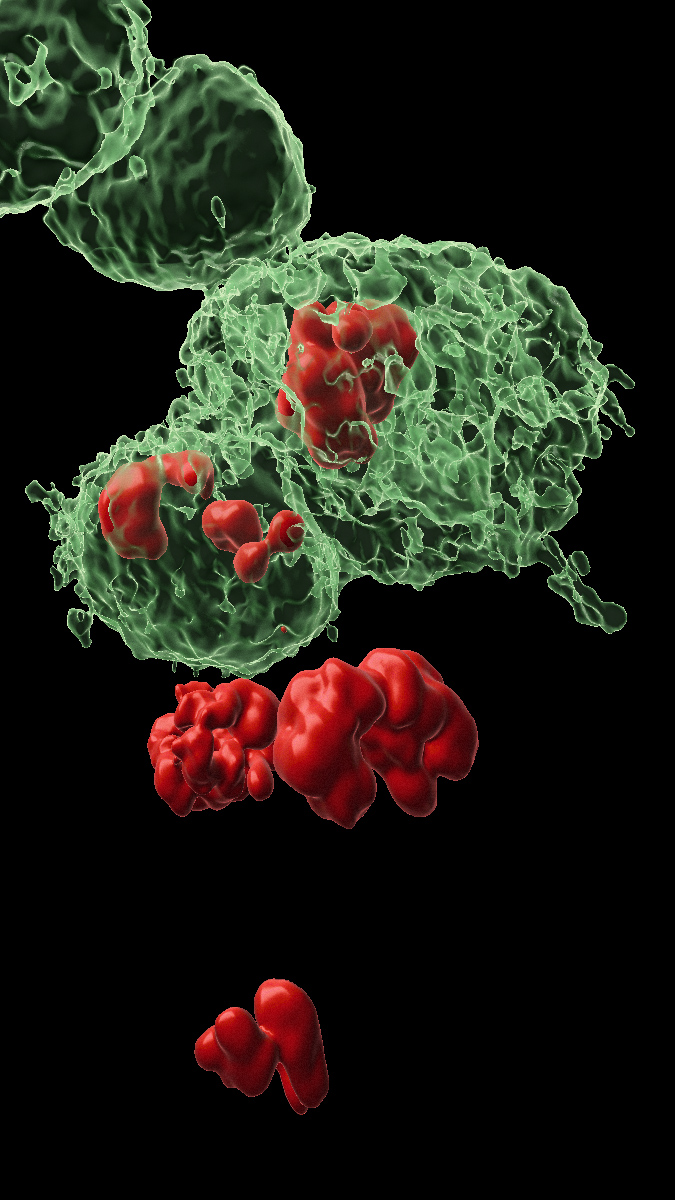

Cellules DARE (marquées en vert) et cellules NARE (non marquées) dans le tissu épithélial à partir duquel se développe l’aile de la mouche. En rouge, les noyaux des cellules en cours de division. Les chercheurs ont découvert que les cellules NARE reçoivent des signaux des cellules DARE voisines leur ordonnant de proliférer.